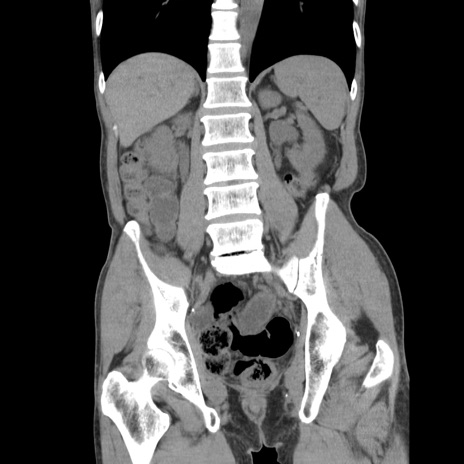

症例11(冠状断像)

【症例】 60歳代男性

【主訴】 下腹部痛

【現病歴】 本日夜中より下腹部痛の症状認め、受診。

【既往歴】 膀胱癌(膀胱全摘+尿管皮膚瘻術) 、胃癌術後

【身体所見】 BT 35.3℃、PR 58/min、BP 136/98mHg、腹部平坦、軟、腸蠕動音±、ストマ留置あり、左上腹部~正中部に圧痛あり、反跳痛なし。

【データ】WBC 5100、CRP0.01